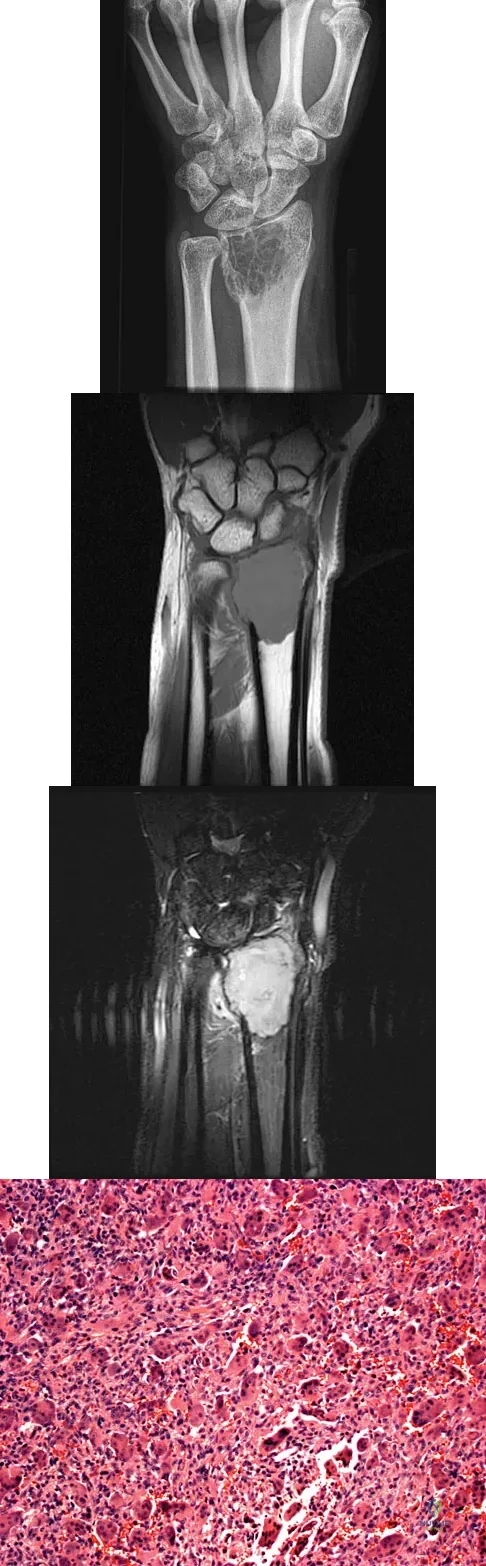

Question 23

A 20-year-old woman has had wrist pain for the past 5 months. A radiograph, MRI scans, and biopsy specimen are shown in Figures 46a through 46d. The patient is then treated with intralesional surgery. The patient should be counseled that her risk of developing lung metastasis is approximately what percent?

Explanation